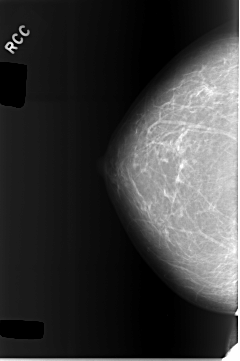

C_0301_1.RIGHT_CC

RIGHT_CC LINES 5768 PIXELS_PER_LINE 3840 BITS_PER_PIXEL 12 RESOLUTION 50 NON_OVERLAY